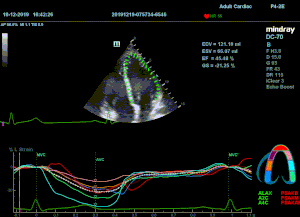

Всё изменилось с появлением технологии Speckle-tracking. Ультразвуковые приборы компании Mindray DC 8, 70, 80, Resona 6,7 оснащены данной функцией. Для использования необходим ЭКГ-канал. В чем же смысл данного технологического новшества? Прибор использует видео петли сечений миокарда, разбивает миокард на точки со стабильной визуализацией – speckle, и затем производит слежение каждой точки в течении нескольких сердечных циклов. Изменение пространства между точками дает нам представление о возможностях деформации миокарда, как продольной – Longitudinal Strain, так и деформации скручивания – торсии и Radial Strain.

На сегодняшний день в мировой клинической практике используется продольный Strain. Методика позволяет выявить нарушения в работе миокарда в каждом отдельном сегменте в среднем до 5 лет раньше клинического манифеста. Так же есть возможность оценки и диастолической функции, с гораздо более высокой чувствительностью чем тканевой допплер. Возможности радиального стрейна изучаются, за этой методикой будущее.

Как работать с данным методом? Для Longitudinal Strain необходимо записать видео петли апикальных сечений в память прибора: 4С, 3С, 2С. Для повышения качества трекинга рекомендуется производить запись на выдохе пациента. Затем произвести разметку по линии эпикарда, перикарда и центра миокарда. Нажатием кнопки «начать слежение» активируется программный алгоритм, видео петля оживает вместе с размеченными точками-speckle’ами. При необходимости производится коррекция. После анализа всех трех сечений можно получить данных продольной деформации как в среднем значении, так и по каждому сегменту миокарда левого желудочка. Нормальным показателем считается Longitudinal Strain -20%. Нижней границей -14%.

Видео примеры на приборе Mindray DC 70